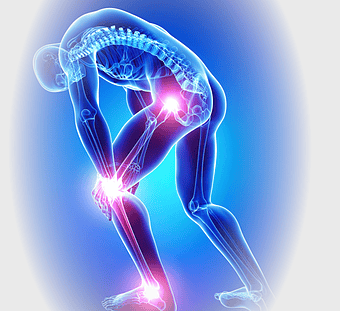

knee pain illustration, osteoarthritis joint pain, medical pain management, violet medical, skeletal joint health, chronic pain therapy, human anatomy injury -

knee pain sports injury, physical therapy for athletes, human knee bones anatomy, joint focus in running, skeletal health in sports, musculoskeletal injury prevention, running biomechanics analysis -

rheumatoid arthritis illustration, chronic pain therapy, joint replacement surgery, blue violet human skeleton, skeletal anatomy diagram, arthritis pain relief methods, orthopedic health visual aids -

arthritis pain symptoms, rheumatoid arthritis illustration, joint pain areas, human body anatomy, skeletal health issues, medical visualization, chronic joint discomfort -